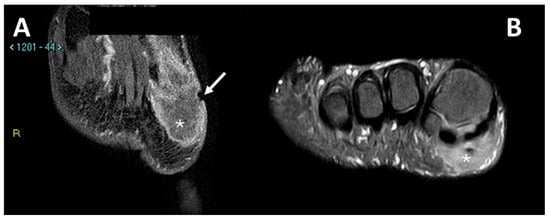

3.4. MRI Features

3.4.1. General MRI Features

3.4.2. Peritumoral Edema

3.4.3. Other MRI Features